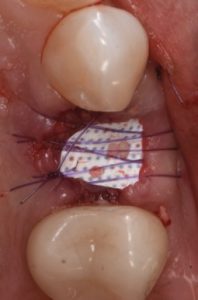

The case features flap management in the presence of a buccal dehiscence, followed by bone graft placement and stabilization using a dense polytetrafluoroethylene (d-PTFE) membrane. Surgical principles, membrane selection, and handling techniques are discussed to optimize ridge dimensions and facilitate future implant placement.

- Indications and advantages of d-PTFE membranes in ridge preservation

- Bone graft placement and membrane stabilization protocols